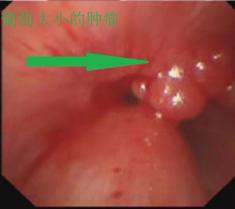

胸部CT及之后支气管镜检查证实了气管内塞满了一粒粒葡萄大小的肿瘤。而且肿瘤向下长到气管胸骨入口以下,即使行气管插管也没有用,如果不积极处理,患者会被活活憋死。

介入手术如期举行,正如吴主任所料,患者根本不能躺下,张绿秀麻醉师只能让患者坐着实施诱导麻醉,麻醉后上官主任在团队娄希贤、朱梦楚、颜晗晗等医生的协作下快速插入硬质支气管镜建立气管通道后,立即实施气道内肿瘤圈套切除术,术中患者血氧饱和度一度下降,在打通一条细小通道后立即置入导丝,成功放置一个覆膜支架,支架释放后患者血氧饱和度立即上升,手术取得圆满成功。